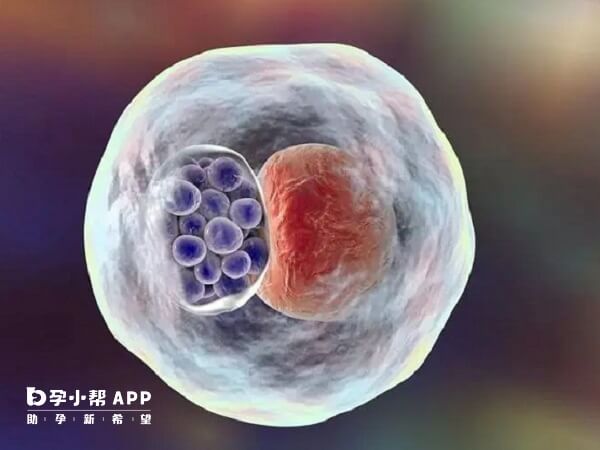

试管胚胎的质量与着床成功率之间存在一定的关系。胚胎的等级是评估胚胎质量的一个重要指标。囊胚有个扩张的腔体,称为囊胚腔。内部可见一团紧密的细胞,称为内细胞团,将来会发育成胎儿。囊胚表面铺满的大量细胞,称为滋养层细胞,将来发育成胎盘。囊胚的等级就根据囊胚腔、内细胞团、滋养层细胞来判定,代表了囊胚的质量和发育潜能。